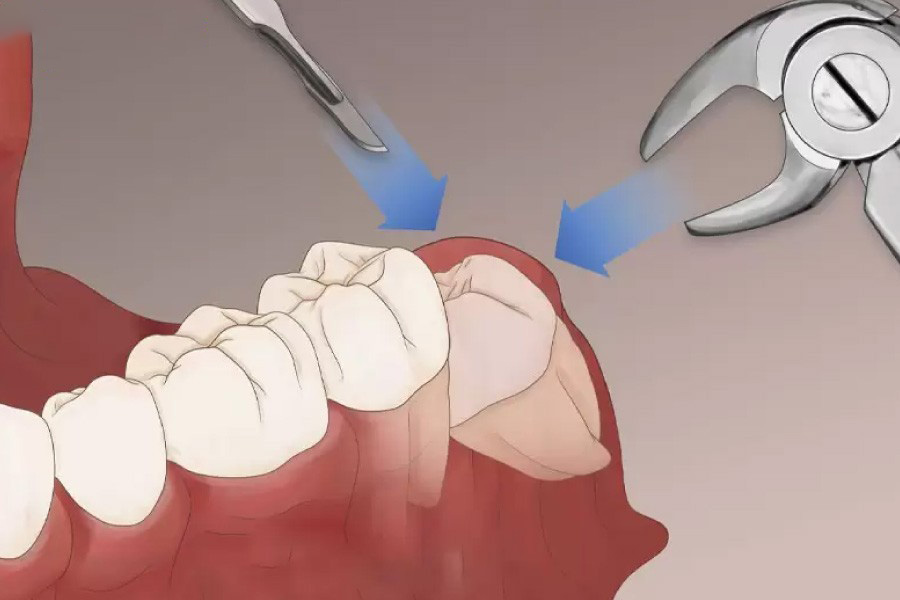

Phẫu thuật nhổ răng khôn thường diễn ra nhanh chóng trong 30 – 45 phút, không đau đớn nên bạn không cần lo lắng quá nhiều.